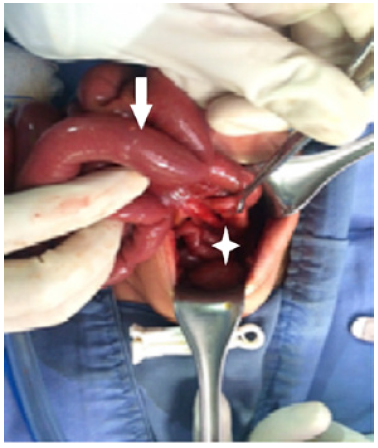

Invasive ventilation was initiated and a nasogastric tube was passed in-situ. An abdominal x-ray showed a large dilated loop of bowel (Figure 2), without a double bubble sign, ruling out duodenal atresia. Based on those findings, in her third day of life, an exploratory laparotomy was performed. A right colon atresia type III (Grosfeld classification) 11 was identified, with a difference of proximal distal caliber from 10 to 1 (Figure 3). A derivative Hartmann's colostomy was performed, given the difference of caliber size that did not allow primary anastomosis. Rectal biopsies were taken, reporting ganglion cells and ruling out Hirschsprung's disease.

Significant colon distension.

Figure 2: Significant colon distension.

Source: Own elaboration based on the data obtained in the study